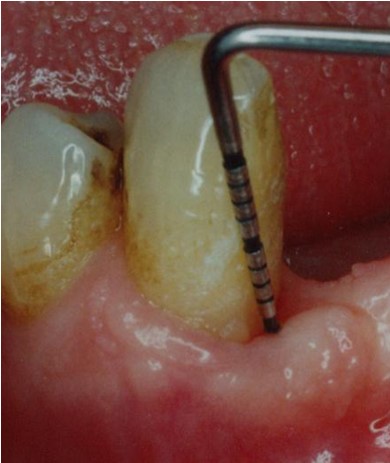

Ovdje treba još napomenuti da se danas u svrhu postizanja optimalnih kliničkih rezultata koriste različite regeneracijske tehnike koje značajno pridonose stvaranju novog parodontna, a time i boljeg estetskog rezultata u usporedbi sa standardnim metodama liječenja (Slika 2).